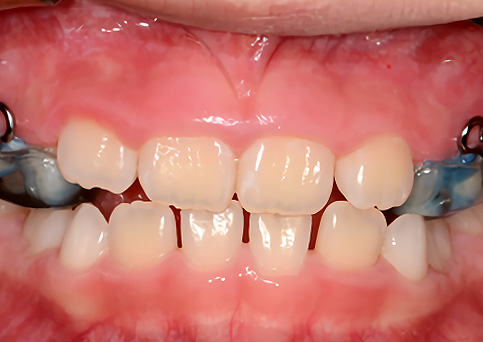

주걱턱

주걱턱, 조기에 예방할 수 있습니다.

페이스마스크를 활용한 악정형 장치로 앞니 반대교합을 개선하고, 주걱턱을 미리 예방할 수 있습니다. 적절한 시기의 예방교정을 통해 자연스럽고 건강한 치열로 성장할 수 있도록 도와주었습니다.

• 주증상

전치부 반대교합

• 치료기간

약 6개월

• 부작용

치아표면의 탈회, 치은 부종, 치근흡수 등의 부작용이 있을 수 있습니다.